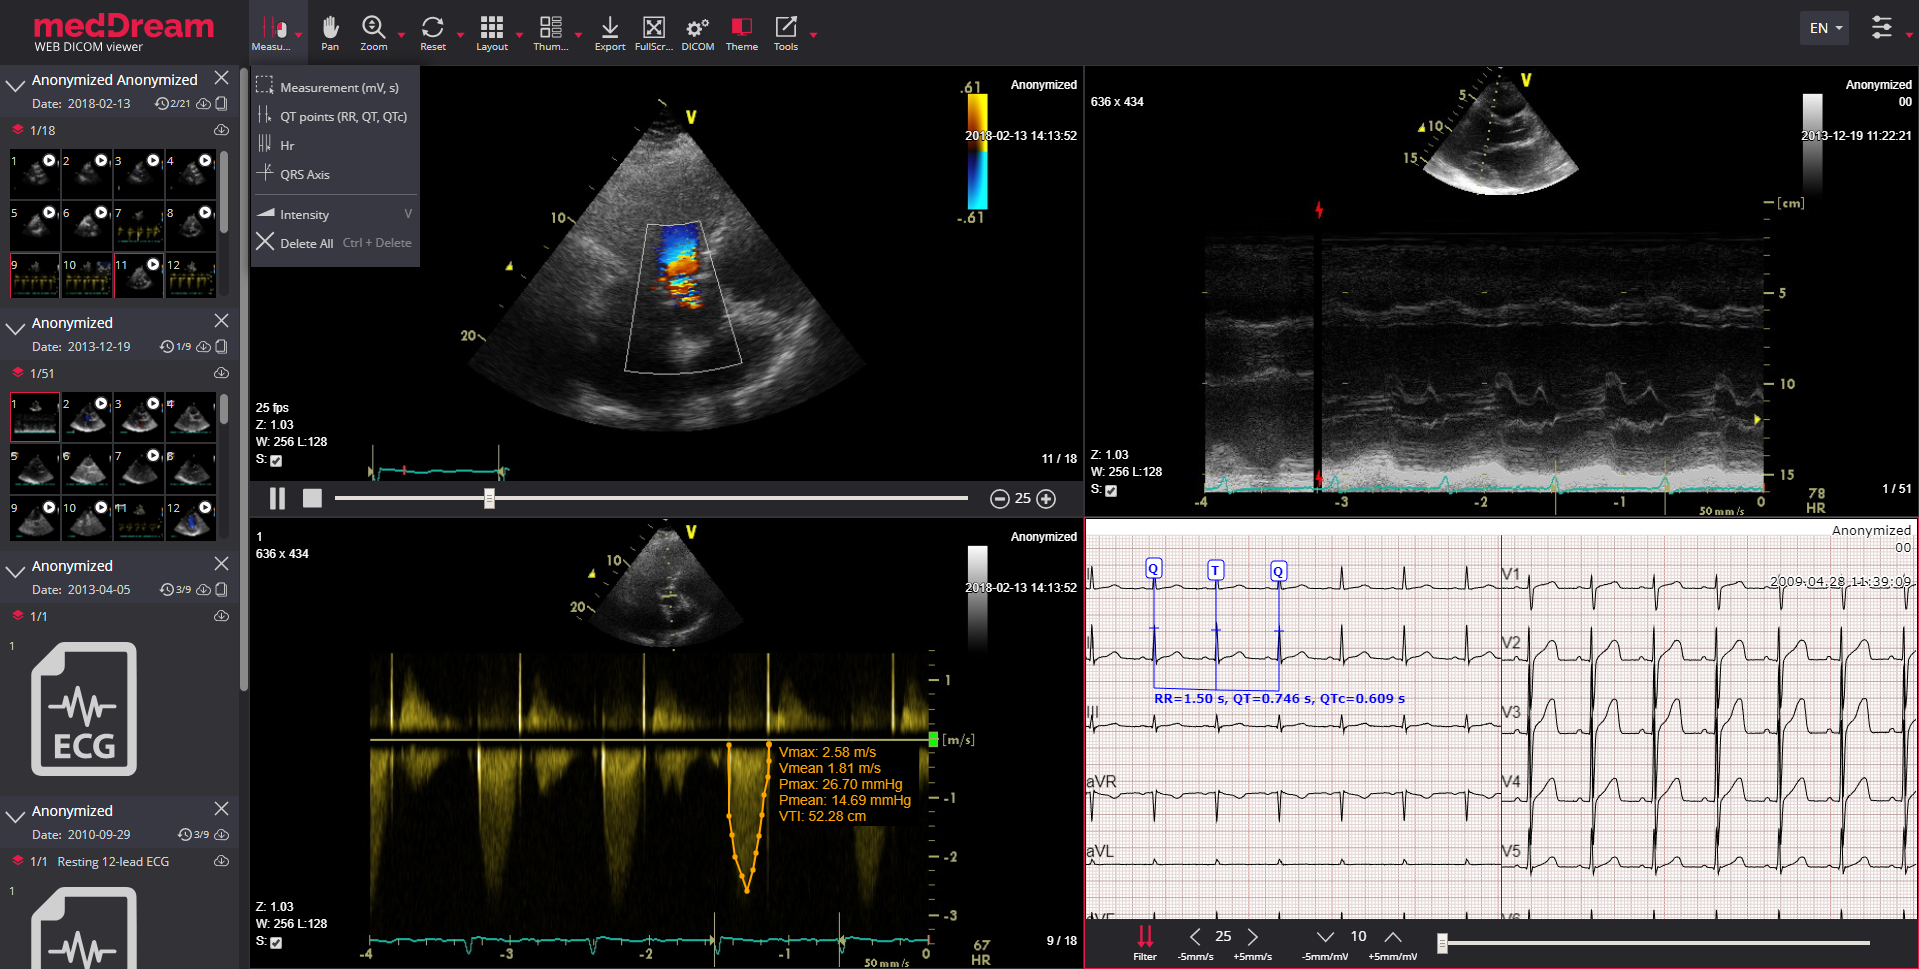

Лазерная камера для печати медицинских изображений на пленке стандарт dicom